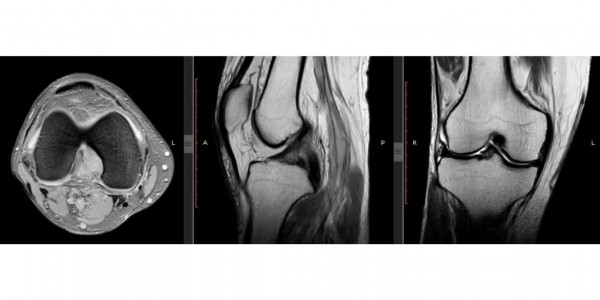

Magnetic Resonance Imaging (MRI) Lutut untuk Evaluasi Ligamen ACL dan PCL

Telusur.co.id - Perkembangan teknologi di sektor pelayanan kesehatan menawarkan berbagai jenis pemeriksaan yang aman dan tidak menyakitkan.